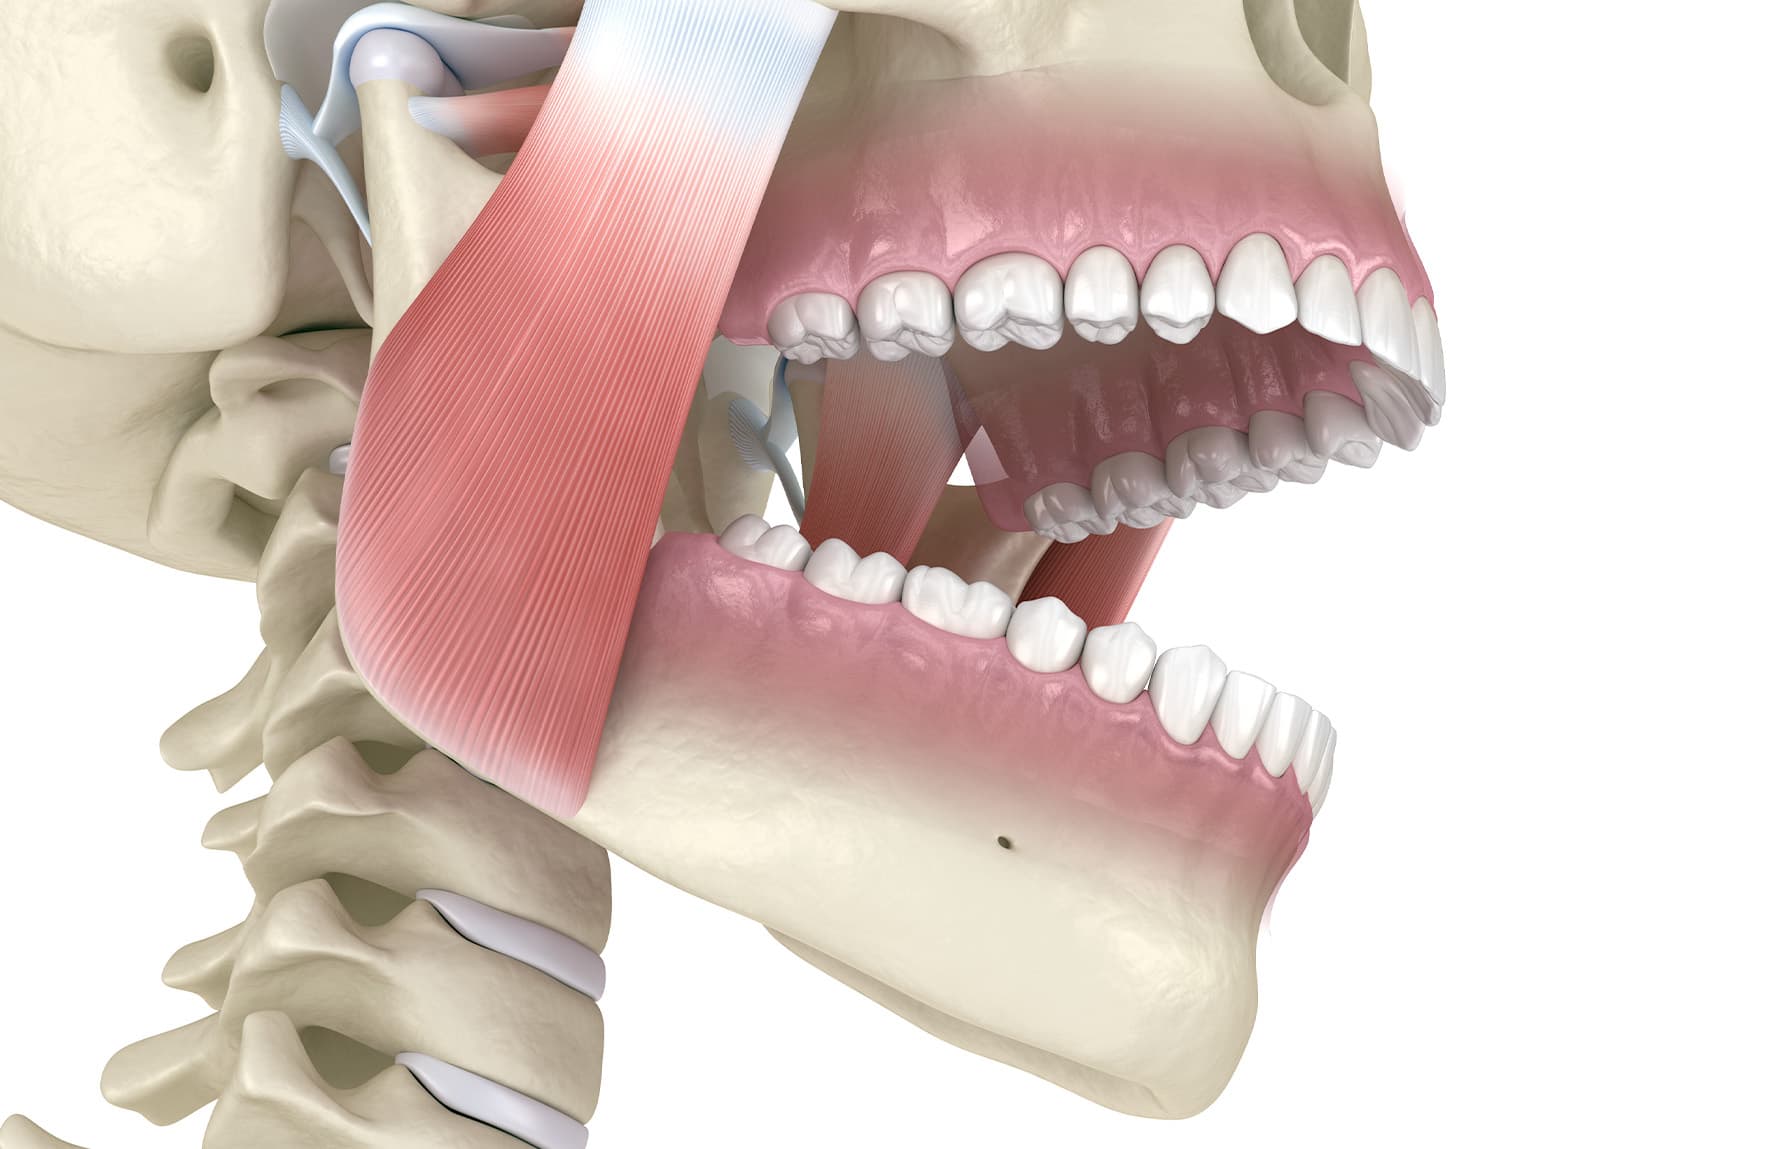

MRA

Een MRA is een speciale beugel die tijdens de slaap gedragen dient te worden. Een MRA brengt tijdens de slaap de onderkaak (lichtjes) naar voren waardoor de luchtweg min of meer open blijft. Tijdens een intake wordt beoordeeld of uw tandheelkundige situatie geschikt is voor een MRA. Afhankelijk van uw zorgverzekeraar wordt er een aanvraag gedaan bij uw verzekeraar om een MRA te mogen vervaardigen, waarbij de kosten worden betaald vanuit de basisverzekering.